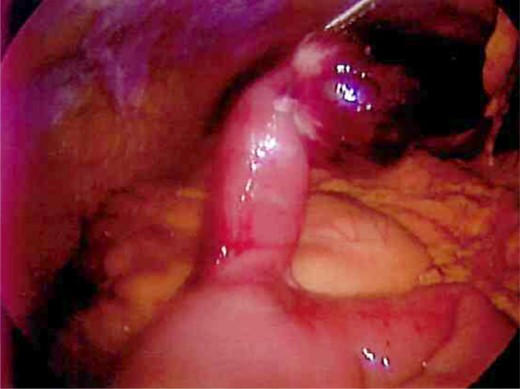

Laparoscopy was performed and a large Meckel's diverticulum was identified ∼30 cm proximal from the ileocecal valve. It had twisted 360° and was swollen and gangrenous at the distal half (Fig. 1). The tip of the diverticulum contained a 3-cm long mesodiverticular band that was attached to the mesentery of an adjacent loop of terminal ileum (Fig. 2). The mesodiverticular band was surgically divided, and the diverticulum was then de-torsed revealing a normal appearing base (Fig. 3). The diverticulum was excised along its base using an endoscopic stapler (Fig. 4). The surgery was completed with an appendectomy. On postoperative day one, the patient was doing well and was discharged home.

Mesodiverticular band connecting the tip of the Meckel's diverticulum to adjacent small bowel mesentery.